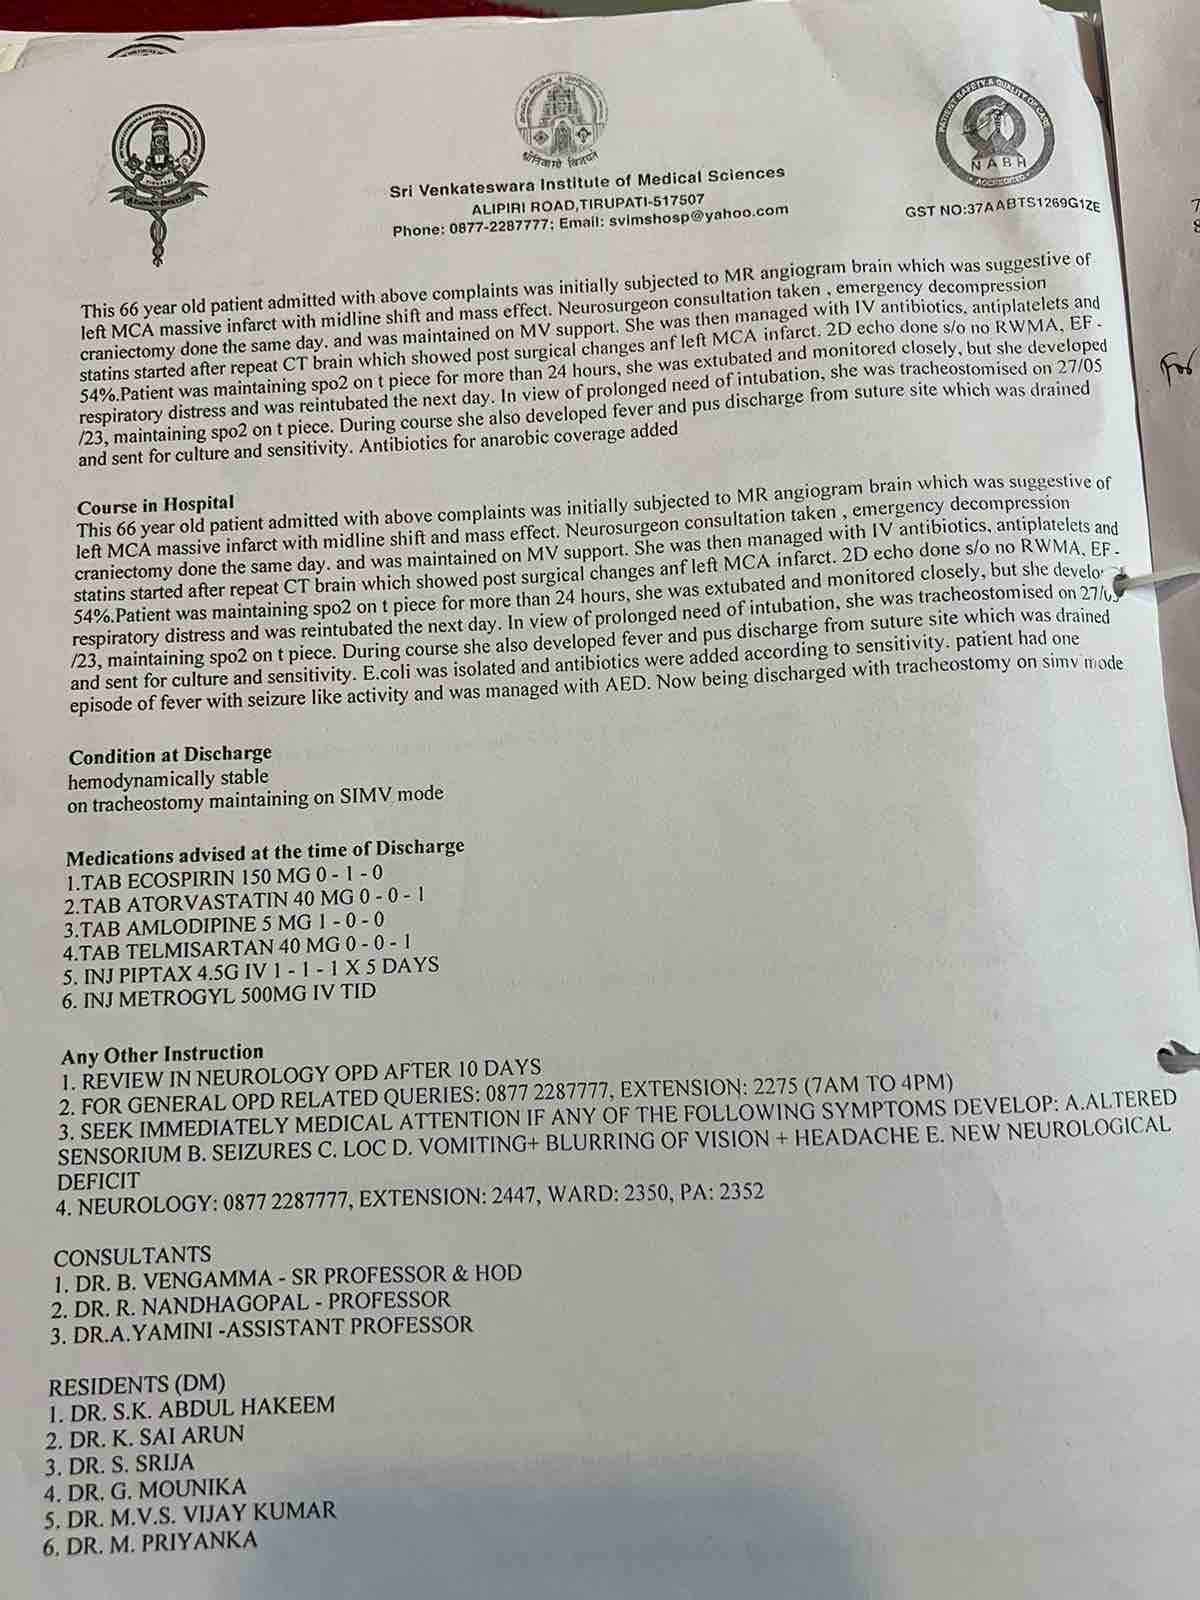

We are reaching out to you today with a heavy heart and a plea for help. Our beloved 66-year-old mother K VIJYA LAKSHMI, has been facing an incredibly challenging journey since 16th May when she had brain stroke & underwent emergency brain and abdomen surgery. Her recovery has been a rollercoaster of ups and downs.

During her hospitalization, she endured multiple complications, including respiratory distress, recurrent severe infections, and even seizure-like activity. Through it all, she has shown immense strength and determination. Still she require three more surgeries to stand on the path of recovery.